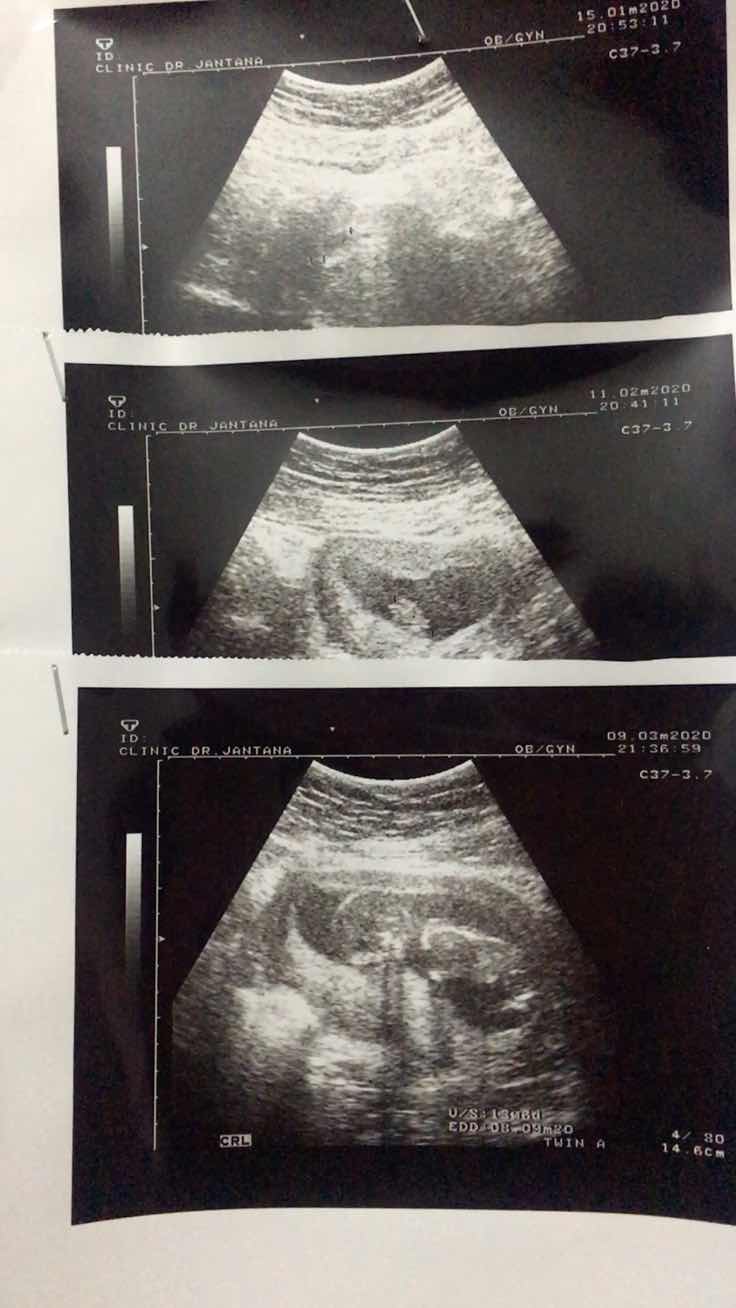

ภาพถ่าย1เดือน2เดือน3เดือน ตอนนี้5เดือนกว่าแล้วจร้าา